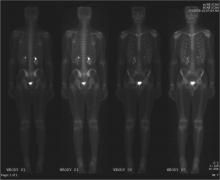

A U.K. National Cancer Research Institute trial has suggested that in patients with early stage Hodgkin lymphoma, the late effects of radiotherapy could be reduced by using a scan to determine those who actually need it. The trial was led from The University of Manchester and the Christie NHS Foundation Trust.